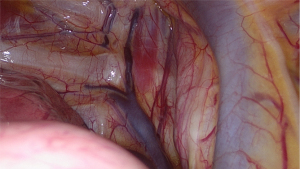

The SVI VATS procedure has been previously published (20). This section briefly summarises the procedure. First, a short-acting muscle relaxant (mivacurium) was introduced, to insert the double-lumen endotracheal tube. During the relaxation period, surgical incisions were made on the right side, as per routine practice, after local infiltration with 2% lidocaine. Subsequently, the following surgical incisions were made: a 3-cm utility incision in the mid-axillary line, a 1-cm submammal fold incision for the camera, and a 5-mm incision for the instrument between the submammal fold and sternum. To block the cough reflex, 5 mL of 0.5% bupivacaine was administered near the right vagus nerve (Figures 1-3), and 4–5 mL was administered between two and five intercostal nerves close to the spine (paravertebral blockade) (Figure 4). After elimination of the short-acting muscle relaxant (mivacurium), the patient breathed spontaneously without coughing, and in some cases, 4–6 positive end-expiratory pressure (PEEP) was administered to maintain perfect oxygenation. During MG, complete thymectomy was performed by removing the thymus and perithymic fatty tissues. As a routine procedure, the right pericardium-diaphragm angle fat, aortocaval groove, and aortopulmonary window fat were removed. Phrenic nerves were identified on both sides. The innominate vein was visualised, and all horns of the thymus were dissected immediately into the neck. Additionally, accessory horns, commonly under the innominate vein, were routinely examined and were not overlooked. The thymus was then dissected up to the left phrenic nerve, which was identified after opening the left pleura using a 30° viewing-angle optical camera. Anaesthesia provided pressure support ventilation (PSV) when the left side was opened, although inspiration and expiration were managed by the spontaneous ventilation of the patient alone (20). The specimen was placed in an Endobag and removed from the thoracic cavity through an axillary incision. At the end of the operation, a 28-Fr chest tube was inserted through a 10-mm port into the operated area.